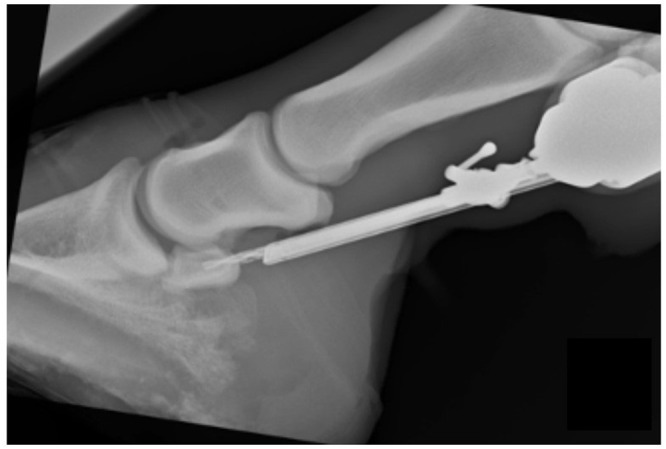

Recently, Bo Brock, DVM, DABVP (equine), from Brock Veterinary Clinic, in Lamesa, Texas, collaborated with colleagues from the College of Veterinary Medicine in Georgia, Colorado State University, and Texas A&M University to evaluate a procedure called core osteostixis. The rationale for this study was that many horses with medullary sclerosis and osseous cystlike lesions of the navicular bone fail to respond to podiatry and/or medical management.

“Osteostixis involves drilling through the cortex of the bone to the medullary cavity,” explains Brock. “It decompresses the medullary cavity. Increased pressure intramedullary may decrease blood flow through the sclerotic cortex.”

Brock et al. conducted a randomized, double-blind, self-controlled trial of seven client-owned horses diagnosed with bilateral podotrochlosis using standard and accepted techniques, including clinical exam, diagnostic analgesia, lack of response to medical management, and MRI. Navicular bursoscopy was performed bilaterally in all included horses, and core osteostixis was performed by drilling a single hole into the medullary cavity of the proximal portion of the navicular bone. If a cyst was present, the hole was drilled directly into the cyst whenever possible. If no cyst was present, the hole was drilled in the middle of the proximal cortex into the medullary cavity, to a depth of 75% the distance between the proximal and distal margins of the navicular bone, being certain not to penetrate the distal cortex.

They hypothesized that the limb with core osteostixis would have a significantly greater reduction in lameness than the contralateral limb that had bursoscopy only. In their study, Brock’s team observed significant improvement in lameness in forelimbs undergoing core osteostixis, suggesting this surgical procedure improved outcomes. Five of the seven limbs in the osteostixis group were sound at 24 weeks compared with only one of seven limbs in the bursoscopy group. On follow-up, MRI showed five of the seven horses that had cystlike lesions bilaterally prior to surgery still had cysts following therapy that remained unchanged. Further, new DDFT tears were identified in three of the seven limbs that underwent core osteostixis.

“I have been performing this surgery for 10 years now and have showed other veterinarians how to do it,” says Brock. “It is technically demanding, which may limit the number of surgeons offering this service, but there are several referral practices and veterinary schools that do.”